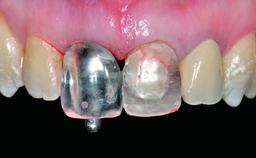

Replacement of a Missing Upper Left Central Incisor: Late Placement of an RC Bone Level Implant, CAD/CAM Zirconia Abutment

A healthy 37-year-old female patient was referred for a consultation on the replacement of missing tooth 21 with an implant-supported restoration. She stated that several years previously the tooth had been traumatically avulsed following a motor vehicle accident. The tooth was replaced with a three-unit fixed partial denture (FPD) immediately afterwards. Over time, she became disillusioned with the FPD and looked for a different option, including orthodontic therapy. She presented still in her orthodontic appliances, with the pontic sectioned free from the FPD but attached to the archwire. Her orthodontist felt that orthodontic treatment had been successfully completed, but nevertheless referred her before removing the appliances in case adjustments were necessary.